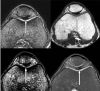

Fig. 3

This image represents four corresponding axial images from different pulse sequences of the left knee. (a) is a T2*-w image, (b) is an ultra short time echo (UTE) image, (c) was obtained with susceptibility weighted imaging (SWI), and (d) represents PD-w imaging with a turbo spin echo sequence. In (a), we note a large area of iron deposit in contact with the patellae and trochlea groove cartilage presented as a low signal intensity focus (arrow). In (b) and (c) we highlight a further exaggeration of the signal loss in the area of iron deposits on the UTE and SWI sequences, respectively (arrows). In (d) we note less conspicuous signal loss of the iron deposit area in the PD-w sequence (arrow)